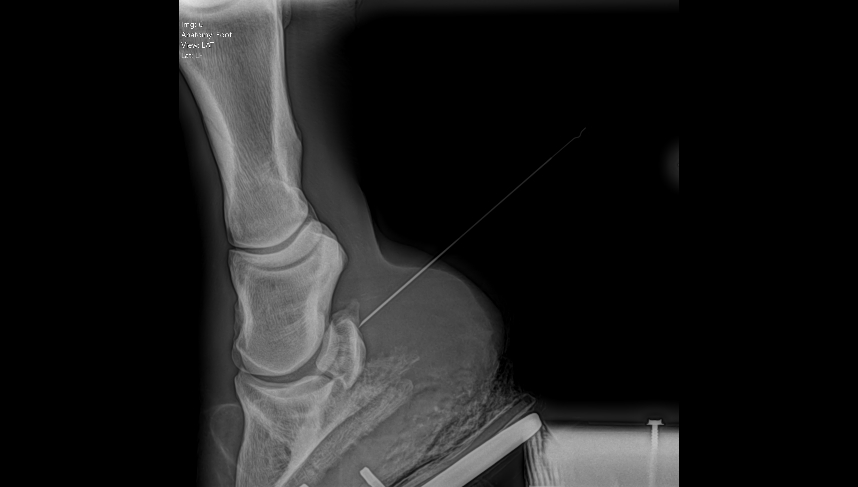

- Detailed lameness diagnostics and treatment, including digital x-rays, tendon/ligament ultrasound imaging, nerve blocking, joint injection therapies, ultrasound-guided treatments, and sport horse performance care.